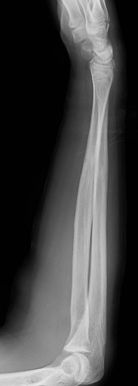

Las fracturas de ambos huesos del antebrazo al mismo nivel, con líneas de fractura oblicua-transversa o desplazamiento convergente son inestables y precisarán de tratamiento quirúrgico. En estos casos está indicado, dependiendo de la edad del paciente, el tratamiento mediante reducción y osteosíntesis. El enclavado intramedular elástico es el tratamiento de elección (Figura 15).

Figura 15: a-Imagen clínica de fractura de antebrazo derecho con gran deformidad. b- Radiografía donde se aprecia fractura de radio-cúbito de trazo transverso en el mismo nivel. c, d-Enclavado intramedular elástico. e,f- Imagen final con buena consolidación ósea.